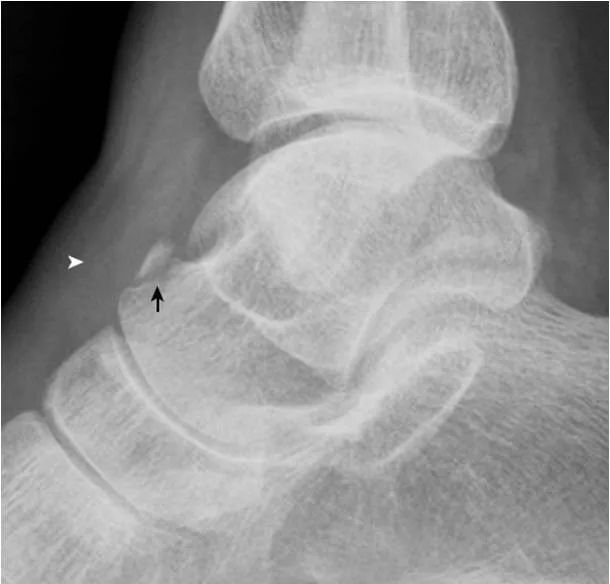

4.跟骨上副骨:

呈跟骨上方、三角骨(白箭头)后方骨性结节(箭),为正常变异。腓骨副骨(黑箭头)与距骨重叠。